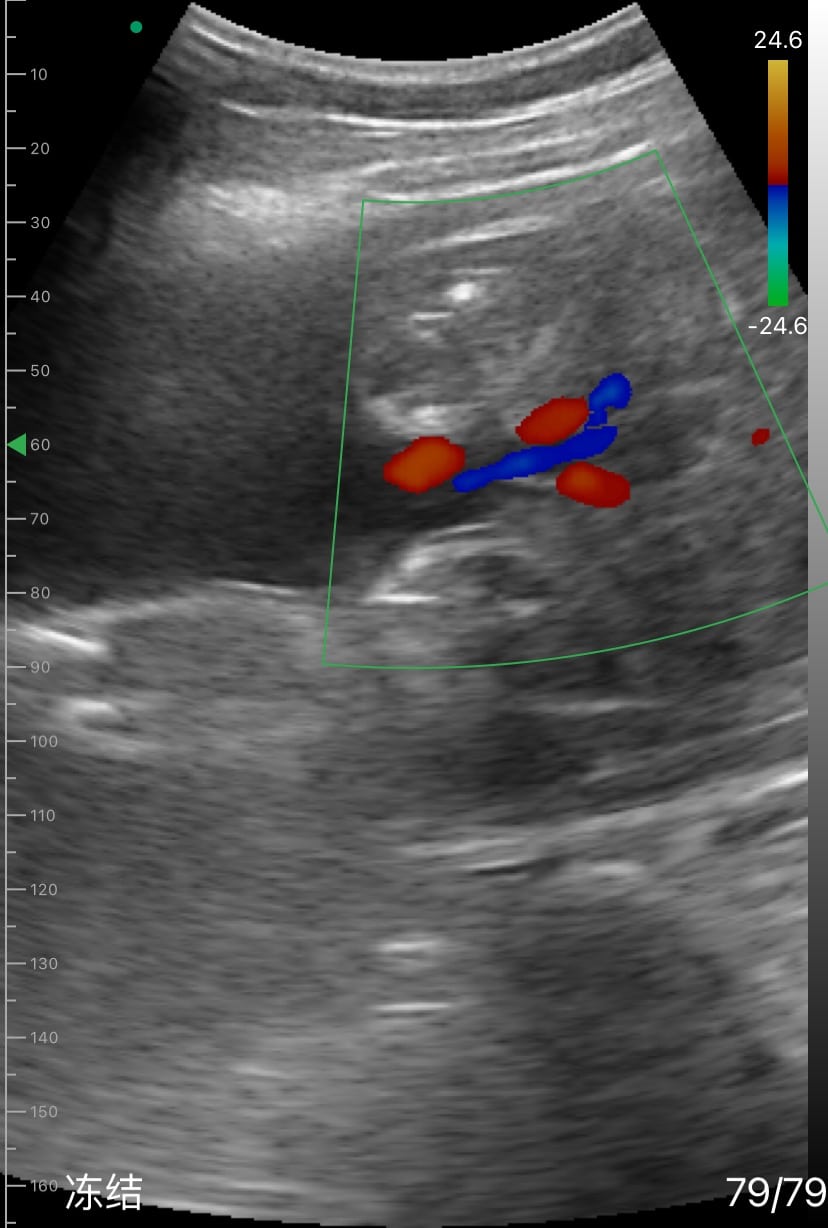

In addition to performing detailed biometric measurements to estimate fetal weight, Dr. Kim utilized the color Doppler mode to assess the umbilical cord blood flow, ensuring proper fetal circulation. She also conducted a thorough evaluation of the fetal spine and lateral ventricles to confirm normal development. Amniotic fluid levels and fetal movement were also checked, providing a comprehensive overview of the fetus's well-being.

In addition to performing detailed biometric measurements to estimate fetal weight, Dr. Kim utilized the color Doppler mode to assess the umbilical cord blood flow, ensuring proper fetal circulation. She also conducted a thorough evaluation of the fetal spine and lateral ventricles, confirming normal development. Amniotic fluid levels and fetal movement were also checked, providing a comprehensive overview of the fetus's well-being.